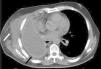

When the patient was admitted to the emergency department of our hospital, he was febrile, and had dyspnea, arterial hypotension, tachycardia and tachypnea, and leukocytosis on blood tests. Chest multislice tomography showed an abscess occupying the entire remaining pleural cavity, impinging on the overlying chest wall (Fig. 1). The patient was hemodynamically stabilized and pleural decortication was performed by video-assisted thoracoscopy. His progress was satisfactory and he was discharged 10 days after surgery.